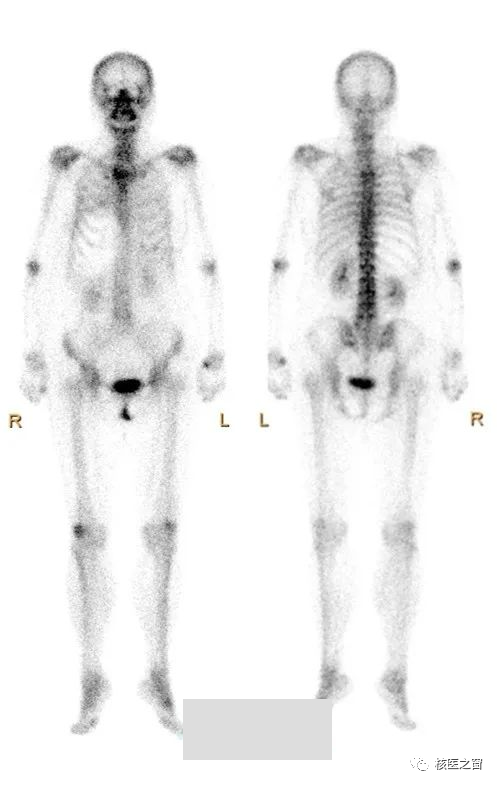

核医学科骨扫描

此时,我们就能够在显示器上看到

骨性关节病的损伤范围、严重性。

骨性关节病早期还是晚期。

相对能够鉴别外伤所致或退行性损伤或自身免疫所致。

对下一步的治疗起到至关重要的指导价值。